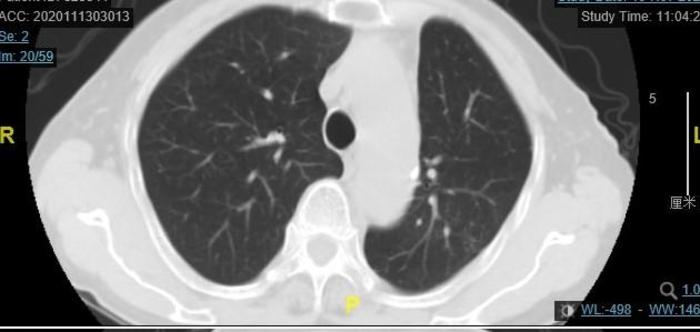

上图为今年9月份住院后的CT,由两张CT组成。上面的CT的蓝色 箭头指向的是混合磨玻璃结节内部有一个腰果形缝隙,所以这个结节不是一个纯实性结节。下面的CT上面两个蓝色 箭头和左下方蓝色箭头指向的是结节内部小空泡(看起来在白色背景中发暗一些)。右边的蓝色箭头指向的是结节外侧有一小块磨玻璃成分。

我对左下方混合磨玻璃结节外侧的一小块磨玻璃成分进行了CT值测量,发现其CT值是-165,因为其CT值是负的,不是正的,证实结节的外侧边缘有磨玻璃成分,所以这个结节一实性成分为主、磨玻璃成分为辅,是一个大型混合磨玻璃结节。即使不就行肺穿刺检查,也有95%的把握这个结节是恶性的肺癌,而且应该已经到了浸润性腺癌阶段。